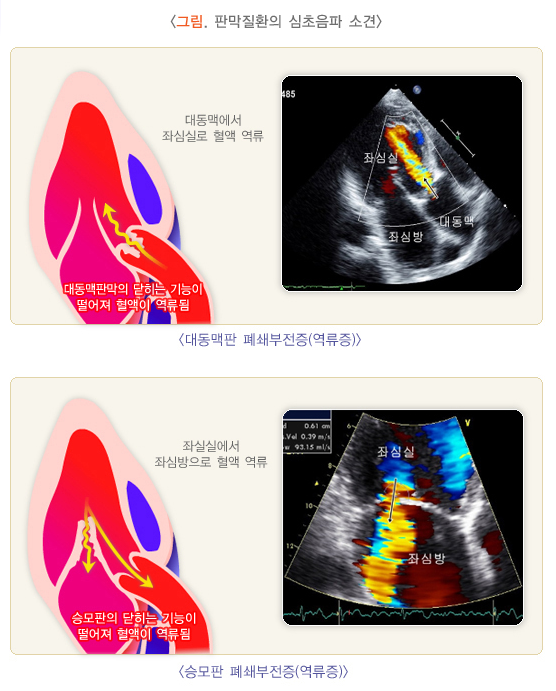

- 승모판의 두께와 크기가 커지며, 형태가 변형될 수 있습니다. 이는 심장 초음파나 심전도 검사에서 확인할 수 있습니다.

- 승모판의 두꺼워짐은 초음파 검사를 통해 정확하게 평가할 수 있으며, 이 검사에서 판막의 비대나 역류 현상을 확인할 수 있습니다.